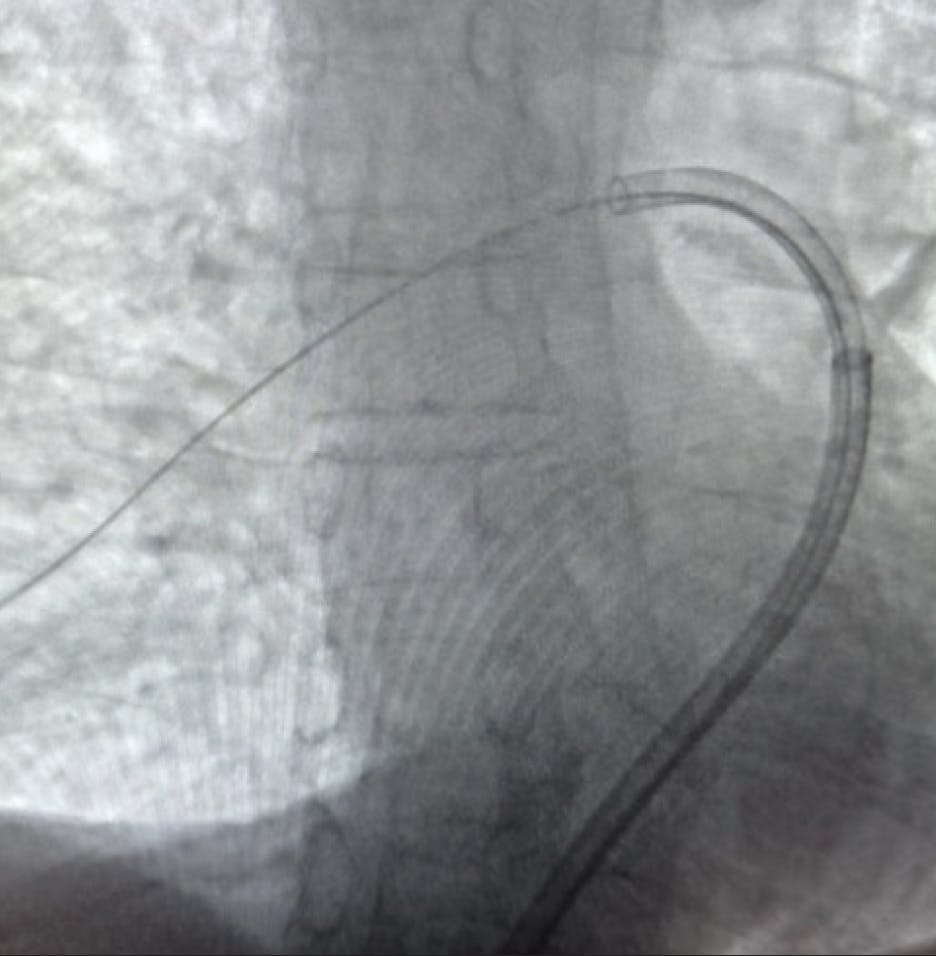

Figure 1. Angiogram depicting the Element sheath in the main PA.

Upon examination, the patient was diaphoretic and experiencing no chest pain. He had elevated troponins, as well as an elevated brain natriuretic peptide (BNP). The patient was contraindicated to thrombolytics due to a recent spinal surgery. CT revealed a massive saddle PE and RV/LV ratio of 2.7, indicating significant RV strain.

Figure 2. Angiogram depicting the Lightning Flash aspiration catheter through the Element sheath.

INTERVENTION

After gaining access in the right common femoral vein under ultrasound guidance, we selectively catheterized the PA over a 0.035-inch exchange guidewire and a 5-F pigtail catheter. We advanced into the distal, right, lower lobar PA, then exchanged the guidewire for a 1-cm, floppy-tip, 0.035-inch stiff Amplatz. Sheath exchange was performed for Penumbra’s 17-F Element sheath and dilator. Element features a HemoLock valve system, designed to ensure hemostasis, and a laser-cut hypotube design to help maintain stepwise support throughout the vasculature. Penumbra’s Lightning Flash 2.0 was inserted, and aspiration was performed in the right main, interlobar, and descending vessels, then into the upper lobar artery. The Element sheath allowed easy access to the left PA, where thrombectomy was performed in similar fashion. After 20 minutes of device time, clot was removed and reperfusion was achieved with an estimated blood loss of 150 mL.